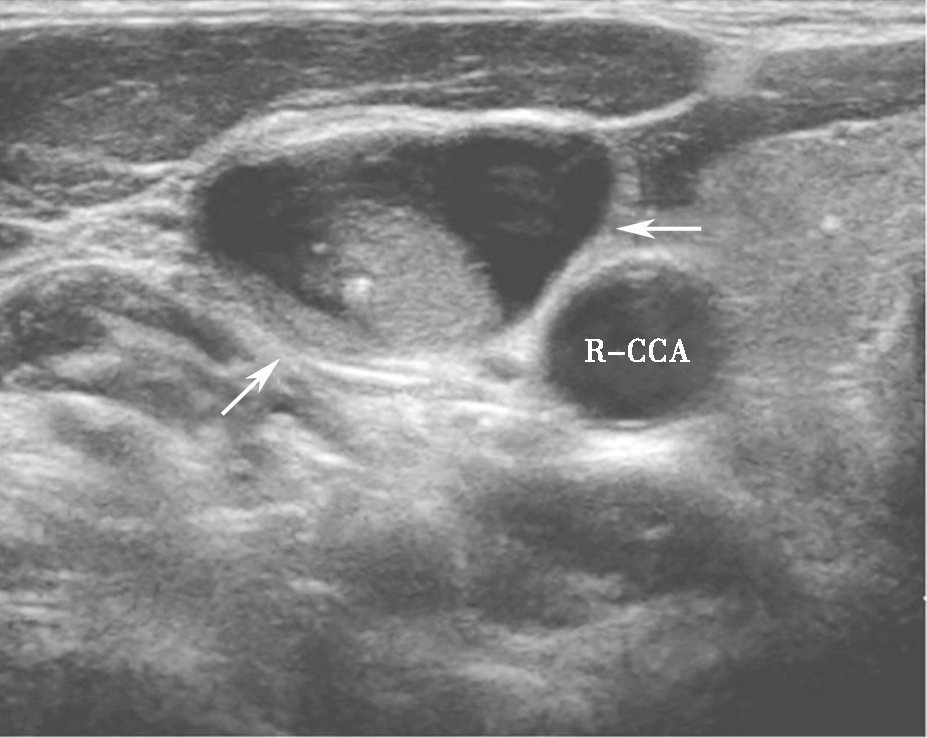

(六)亚急性甲状腺性炎

亚急性甲状腺炎超声表现为腺体内片状低回声,边界模糊,内可有散在的稍强点状回声,探头挤压时有压痛(图5)。低回声以外腺体彩色多普勒血流信号基本正常,低回声内部血流信号轻度增加或无明显增加,周边无明显血管绕行,部分低回声内部可显示正常甲状腺血管穿行。患者可伴有颈淋巴结增大。

R-CCA:右侧颈总动脉,T:气管.jpg)

图5颈部正中偏右侧横切面:甲状腺右叶饱满,可见片状低回声,边界模糊(箭头所示)R-CCA:右侧颈总动脉,T:气管